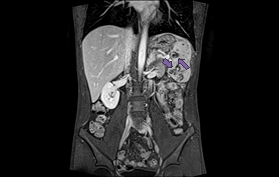

Further imaging by MRI Abdomen showed Bulky spleen demonstrating lobulated and nodular outline with multiple intra parenchymal focal lesions of variable size and many of them appears conglomerate and ill-defined identified throughout the spleen. These lesions are predominantly hypointense in T1 and T2-WI with faint areas of high T2 signal and heterogeneous enhancement. Multiple subcentimetric and/or borderline size lymph nodes are identified at the left para-aortic region, portahepatis, posterior to the gastric fundus and left anterior supradiaphragmatic region the largest measuring 10 mm in short axis (left para-aortic) at SMA level (Figure 2).

Figure 2 Axial T2 and multi-planer contrast enhanced T1 Fat suppressed images of the abdomen showing a bulky spleen demonstrating a lobulated outline with multiple conglomerated intra parenchymal focal lesions of variable sizes showing predominantly hypo-intense signal on T1 and T2-WI with faint areas of heterogeneous enhancement.